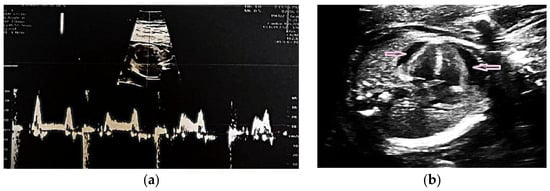

Fetal echocardiography confirmed CAVB with a ventricular rate of 64 bpm (Figure 1a). Subsequent maternal serologic evaluation identified anti-Ro/SSA and anti-La/SSB antibody positivity, indicating an immune-mediated etiology. In the absence of systemic manifestations or laboratory findings suggestive of systemic lupus erythematosus, a primary diagnosis of Sjögren’s syndrome was considered.

Figure 1. (a) Fetal echocardiography at 20 weeks of gestation with CAVB with a heart rate of 64 beats per minute (bpm); (b) Fetal echocardiography at 24 weeks of gestation showed a heart rate of 59 bpm, cardiomegaly and pericardial effusion (pink arrows).

Treatment was initiated with oral dexamethasone (4 mg/day) and salbutamol. The medical team evaluated fetal pacemaker placement through invasive intrauterine intervention, but it was considered inappropriate owing to early gestational age, fetal size, and high procedural risk [18,19,20]. Follow-up fetal echocardiography at 24 weeks showed progressive cardiac deterioration, with the ventricular rate decreasing to 59 bpm and echocardiographic evidence of cardiomegaly and pericardial effusion (Figure 1b). Intrauterine fetal demise occurred at 25 weeks.